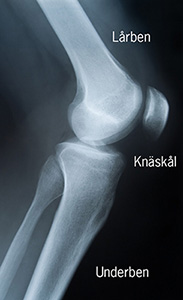

Diagnosen kan ställas med bakgrund av dina symtom och i ett senare skede av sjukdomen genom en vanlig röntgen.